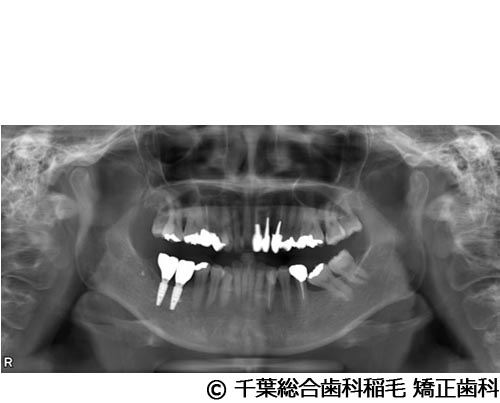

【症例5】All-on-6(オールオン6)

- 治療前

- 治療後

- 治療名

- All-on-6(オールオン6)

- 費用

- 7,500,000円(税込)

- 期間

- 10ヵ月

治療内容

-

患者様の症状

入れ歯が合わなくなり、お食事も満足にできないとご来院されました。

治療法

ご相談の結果、上顎はインプラントを6本、下顎は7本埋入し、All-on-6(オールオン6)という固定式のインプラント治療を行いました。

治療結果

入れ歯が動いてしまう煩わしさがなくなり、よく噛めるようになったと仰っています。

※治療結果は患者様によって個人差があります。